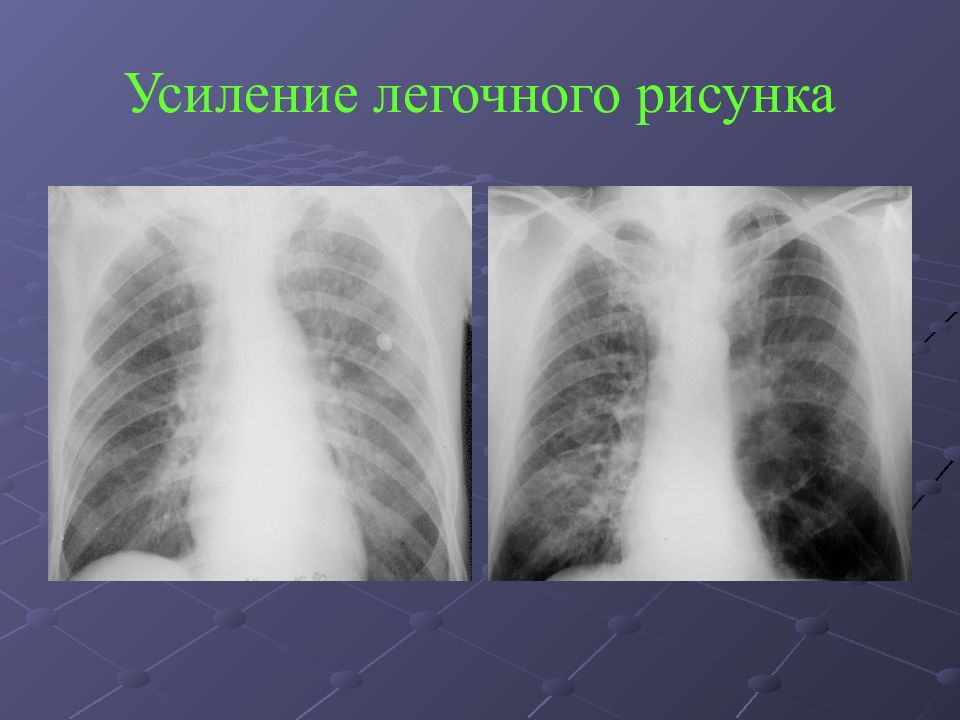

Ячеистая деформация легочного рисунка: медицинская визуализация